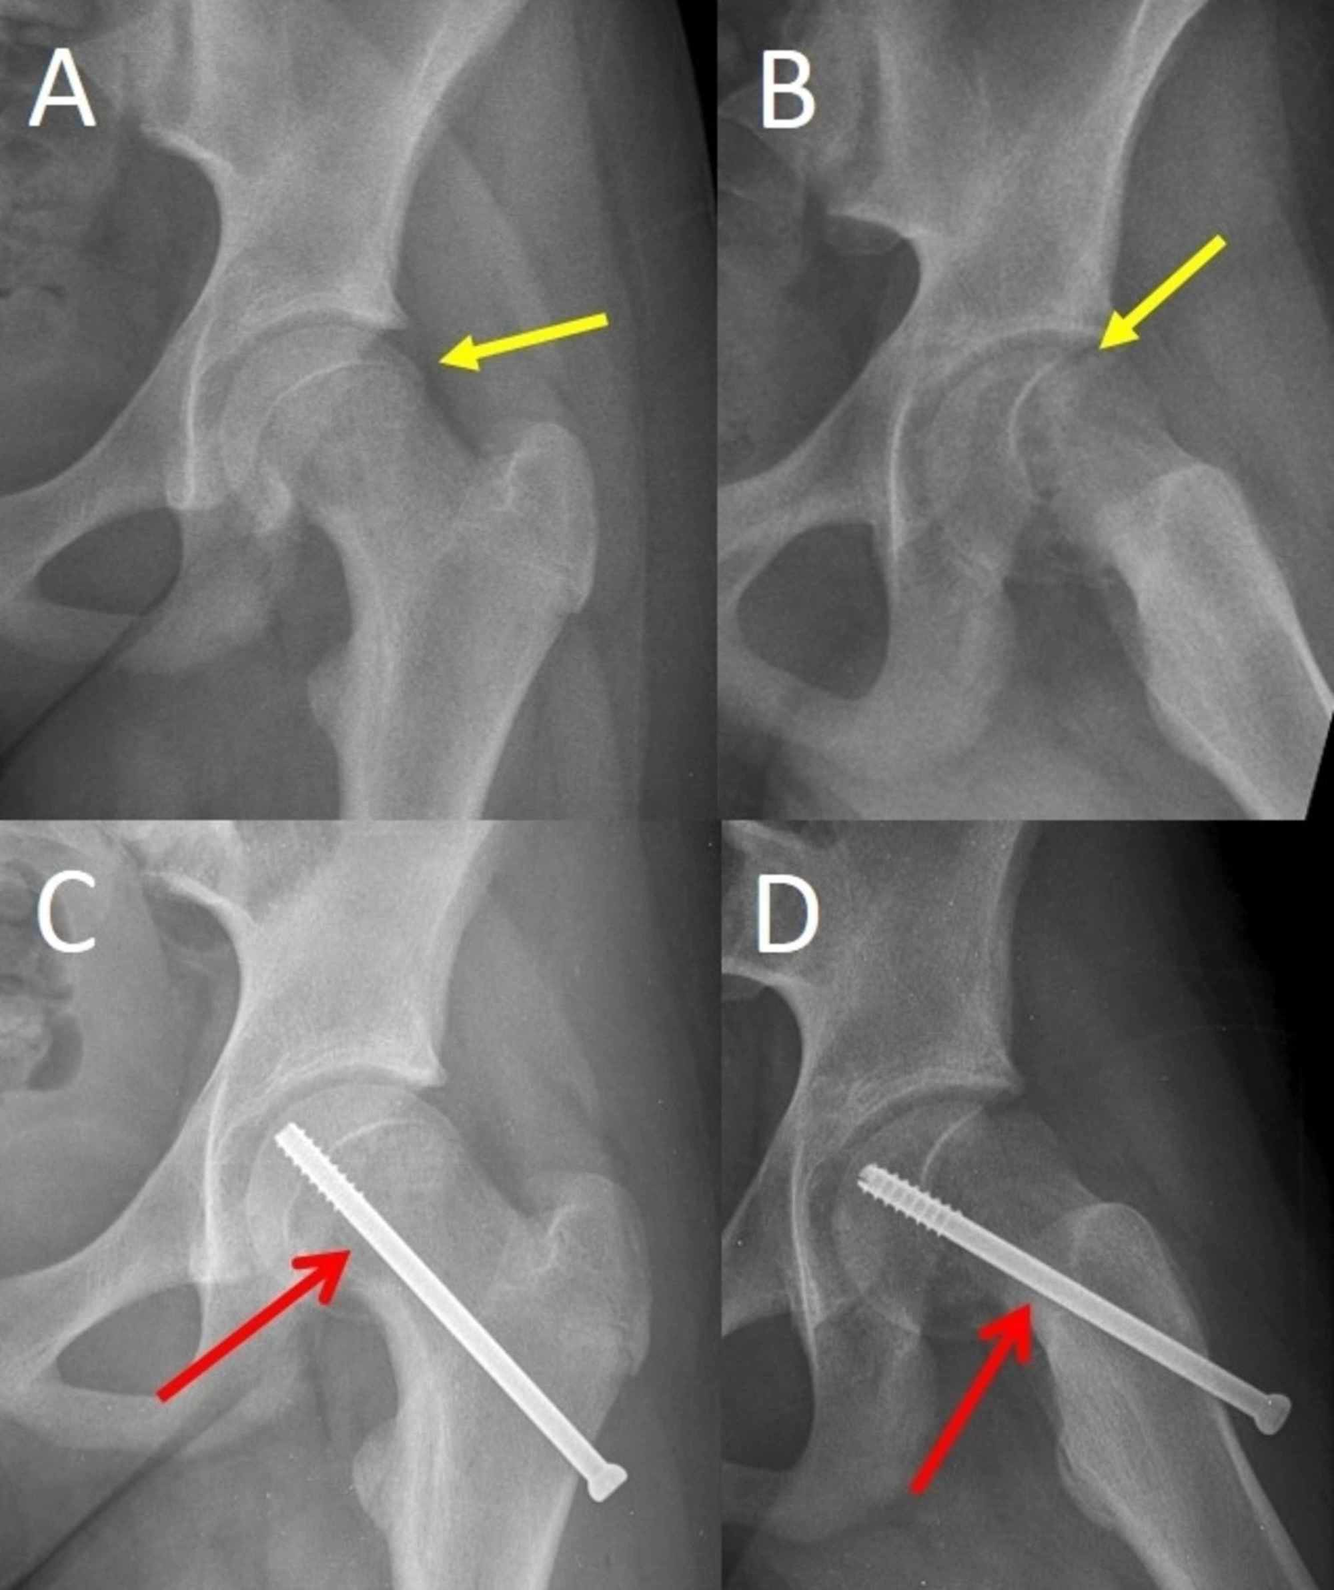

SCFE lesion

Slipped capital femoral epiphysis (SCFE)